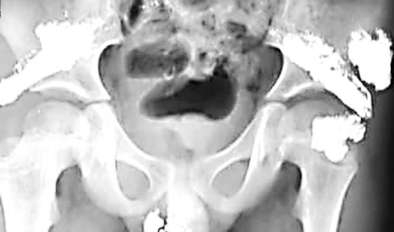

這些“亮晶晶”的東西讓于先生感到很奇怪,為了查明原因,2月5日,于先生帶希希來到昆明醫(yī)科大學(xué)第一附屬醫(yī)院檢查。據(jù)X光片檢查結(jié)果顯示,希希體內(nèi)含有大量金屬物質(zhì),經(jīng)醫(yī)院診斷,這些金屬是汞,也就是俗稱的水銀。

希希體內(nèi)存在的水銀,分布在臀部很多位置,且數(shù)量驚人。一位護(hù)士告訴于先生,希希臀部的水銀量,“最起碼有百八十只溫度計(jì)中的水銀含量”。